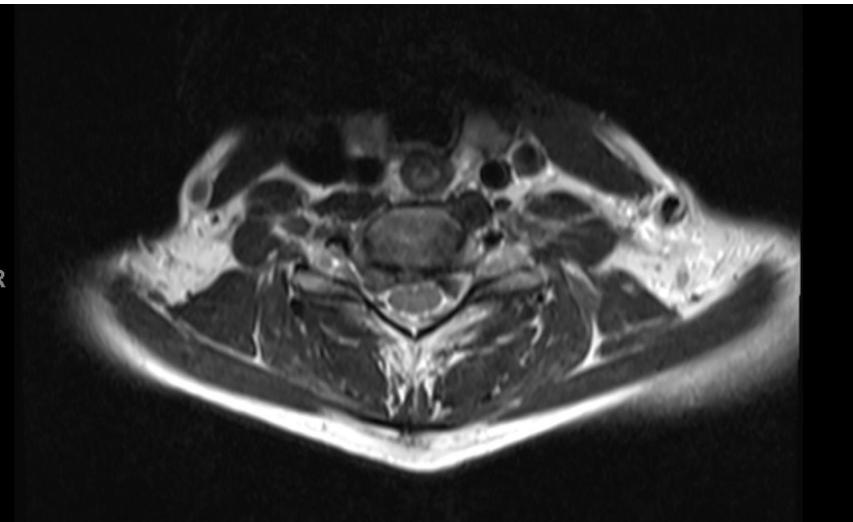

Lumbar Disc Herniation

- Significance: Very common cause of low back pain and unilateral leg pain (radiculopathy)

- Diagnosis: Made clinically and confirmed with MRI studies of lumbar spine

- Initial treatment: Nonoperative with oral medications and physical therapy for radicular leg pain

- Surgical indication: Microdiscectomy for severe pain and/or motor deficit that have failed to respond to nonoperative management

L5/S1 Disc Herniation Example: